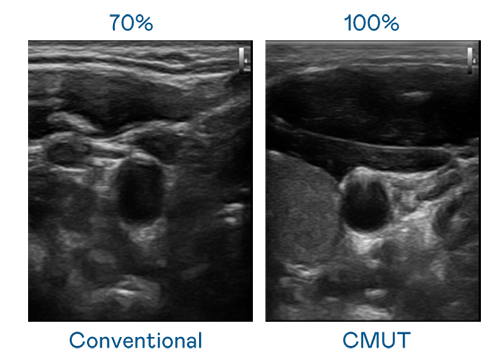

CMUT 技術是一種用電容式微機電元件來產生超音波訊號的技術。與傳統 PZT 壓電式技術相比,CMUT 頻寬增加 30%,更寬頻的超音波訊號讓影像解析度大幅提升,是實現高影像品質醫療超音波掃描、促進精準醫療發展的關鍵技術。

超音波影像的解析度高低,首先取決於探頭能發出的訊號頻寬。3377体育 CMUT 可提供高清晰的超音波訊號,提供高頻寬、高靈敏度、影像紋理細節更高的超音波影像,協助醫護人員縮短影像判讀時間及利用精準的醫療影像進行診斷。